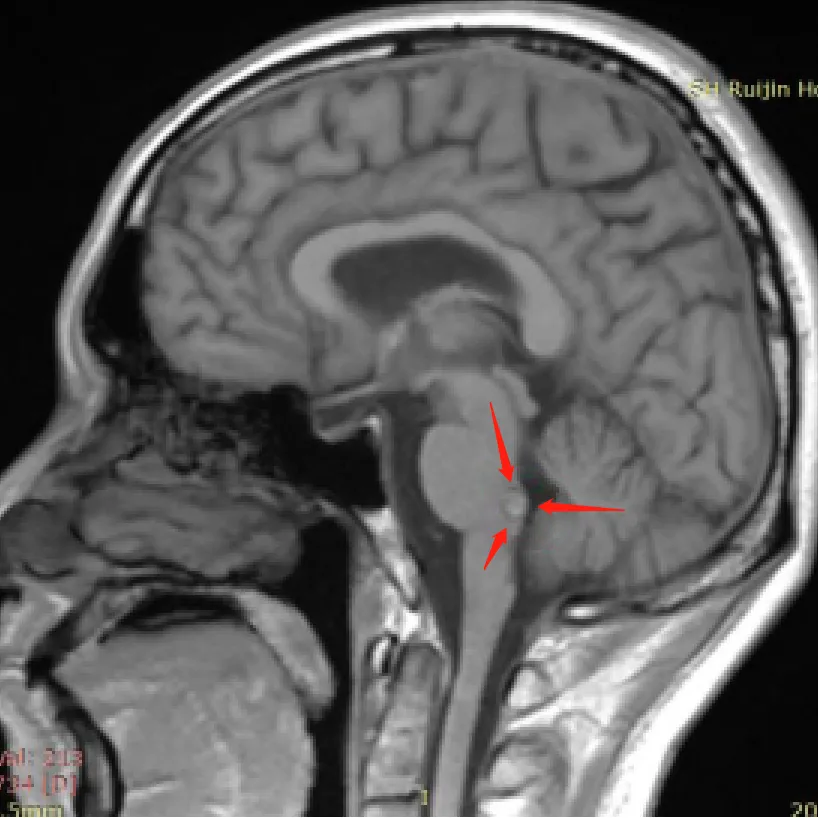

诊断:脑干海绵状血管瘤

术前张先生已出现身体控制障碍征兆:行走不稳需扶墙移动;视力模糊视野受限;术前谈话时甚至需要家属搀扶才能就座——这些症状提示脑干病变已影响运动及视觉功能。

随后由巴特朗菲教授主刀,国内神经外科团队协同配合,成功切除这例高风险脑干海绵状血管瘤。